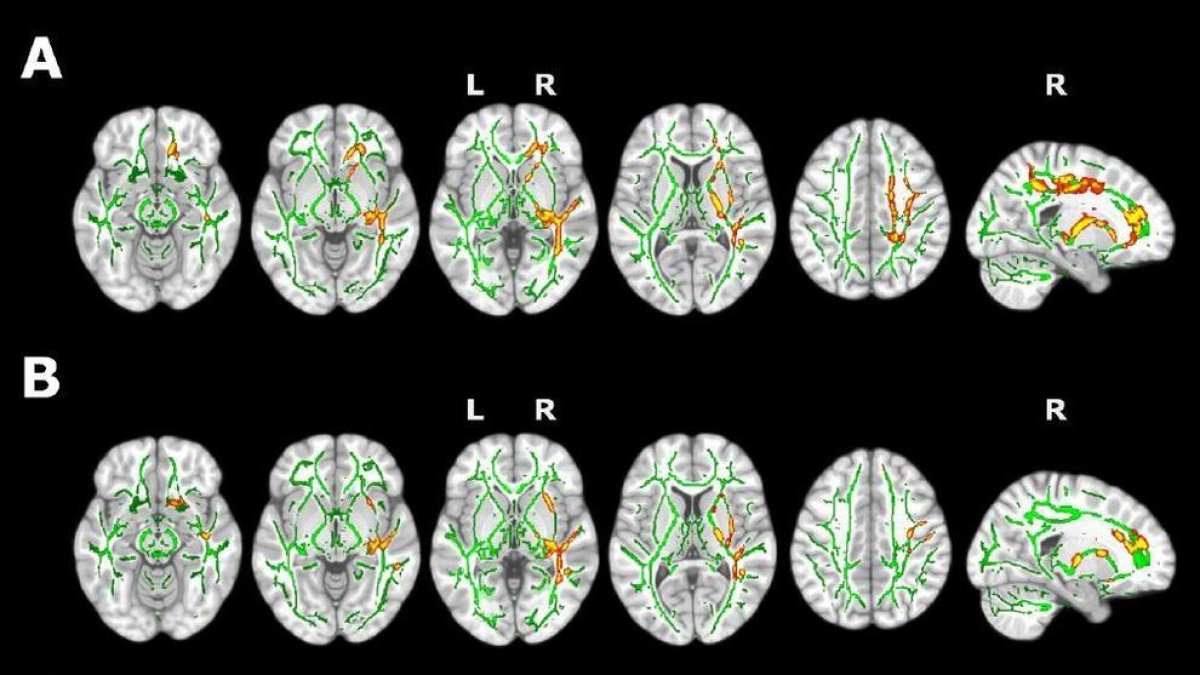

A través de imágenes de resonancia magnética, el estudio demuestra que los participantes presentan un menor volumen en algunas regiones cerebrales, como el preúneus o el córtex cingulat, que se encuentran afectadas en las primeras etapas de la enfermedad del Alzhéimer y de esta manera, se da apoyo a las investigaciones que relacionan la presencia de insomnio con una elevada vulnerabilidad a la enfermedad de Alzheimer. El estudio también ha encontrado cambios en la sustancia blanca cerebral mediante técnicas de resonancia magnética por difusión que sugieren, según el primer autor del estudio, Oriol Grau, la presencia de procesos de inflamación cerebral que podrían tener un papel clave en la asociación entre la calidad del sueño y la enfermedad. Por eso, considera que se abre una nueva línea de investigación que hasta ahora no había sido explorada, para entender la relación entre la neuroinflamación, el sueño y la demencia.